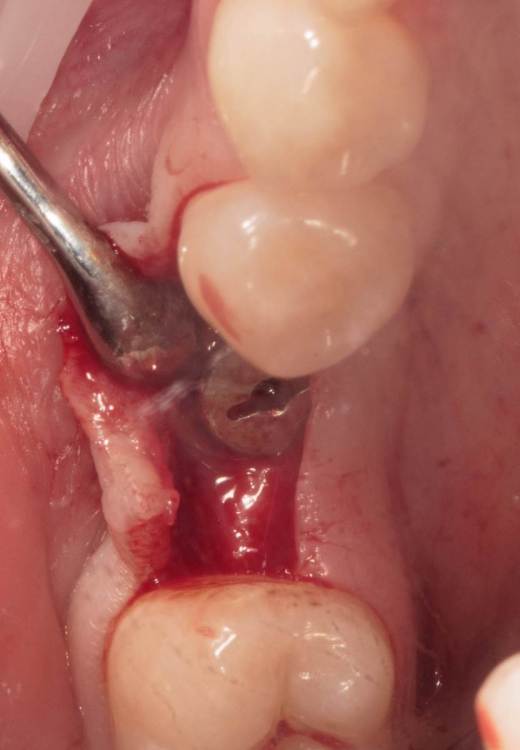

Женька Опубликовано 19 августа, 2023 Поделиться Опубликовано 19 августа, 2023 ?️. Поймал себя на мысли, что испытываю проблемы с ушиванием+ССТ на формике. А именно-не устраивает результат "прирощённой" десны. Вроде на ушивании есть + к объёму, а на протезировании "яма" вестибулярно лишь немного уменьшилась. Подскажите, как лоскут формировать так, чтобы в слоёном пироге имплантат-формик-сст оставался объём слизистой, а не таял. Подумал, что может стоит при имплантации сразу формировать асл. А в кейсе я снова "согрешил" и поставил ультра-низкий формик. В этот раз без всяких послаблений лоскута и натяжения, кмк. Ссылка на комментарий

Женька Опубликовано 21 августа, 2023 Автор Поделиться Опубликовано 21 августа, 2023 @annda вот тут всё по одному месту пошло в попытке закрыть эти низкие фдм. Ссылка на комментарий

Женька Опубликовано 21 августа, 2023 Автор Поделиться Опубликовано 21 августа, 2023 @annda да не, там всё стык в стык пассивно ушилось. скорее это потому, что "ножка" в воздухе просто висела по сути, прикрепиться не к чему, вот и до свидания Ссылка на комментарий

Женька Опубликовано 19 ноября, 2023 Автор Поделиться Опубликовано 19 ноября, 2023 (изменено) прошло 3 месяца. Изменено 19 ноября, 2023 пользователем Женька порядок фоток 1 Ссылка на комментарий